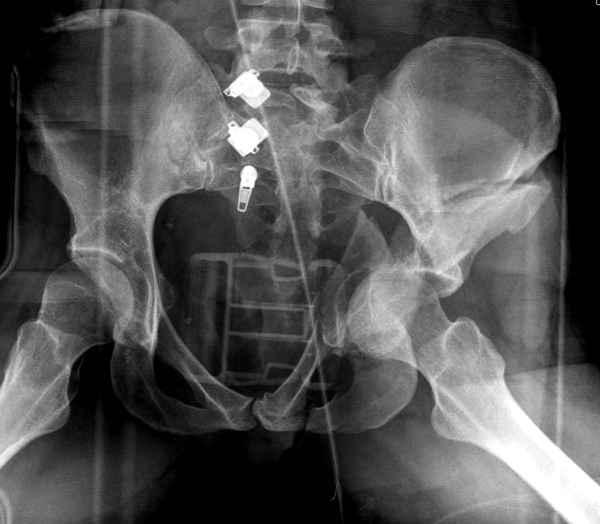

Интересно было бы посмотреть рентгенограммы до операции. У меня впечатление, что я не все вижу, что тут есть... Уважаемые Господа "тазисты" и "тазологи", к какому типу переломов вертлужной впадины по Летурнелю вы бы отнесли это случай?

Поэтому хотелось бы дообследовать больного (разумеется включив стандартные проеции judet,и срезы показывающие сращение)

И наконец главное- какие жалобы у пациента, он нагружает ногу или нет, какая клиника, что-то все рентгенограмму бросились лечить?

Может он спокойно походит на своем суставе и для протеза еще не созрел?

Пациент передвигается с помощью костылей с дозированной нагрузкой на правую ногу. При движении правой нижней конечностью ощущает щелчки. Болей в правом тазобедренном суставе в настоящее время нет. Вся правая нижняя конечность умеренно ротирована наружу.

Хорошо бы на рентгенограммы взглянуть и побольше срезов по своду. С каким отломком головка контактирует и как ее состояние.